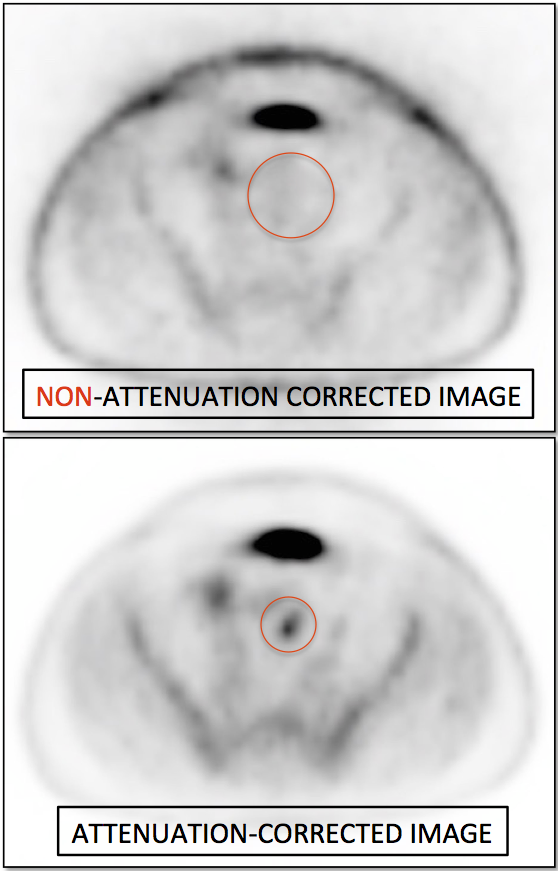

Value of Non-Attenuation Corrected (NAC) Images

Resolving Attenuation Correction Artifacts:

The CT images obtained during an exam are not only used for “anatomic” interpretation. They are also used for “attenuation correction” (AC) of the PET images, generating the much more useful AC PET images used for interpretation.

Unfortunately, attenuation correction of PET images can result in falsely elevated metabolic activity in regions of high CT density (e.g. metallic devices, oral contrast, calcification).

In such cases, these areas must be reviewed on the NAC (non-attenuation correction) images. If these regions are not also hypermetabolic on the NAC images, then their apparent increased FDG-uptake on the AC images is artefactual.

This phenomenon is almost exclusively seen with older PET/CT scanners, as most modern scanners utilize newer algorithms that do not “over-correct” in these areas of increased density.